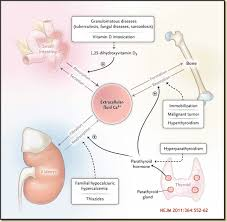

2. Hypercalcemia & Hypercalciuria

Sarcoidosis can increase vitamin D activation, leading to:

- High calcium in the blood (hypercalcemia)

- High calcium in the urine (hypercalciuria)

Excess calcium strains the kidneys and increases the risk of stones and kidney damage.